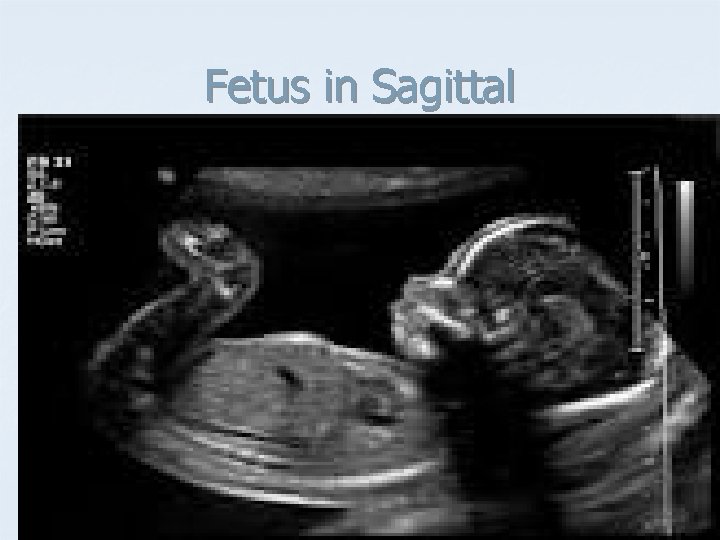

Fetus in Sagittal